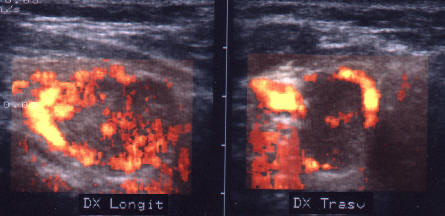

Carcinom midUlar

Lob stang, proiectie trasversala si longitudinala

Barbat de 55 ani. Formatiune nodulara voluminoasa ce ocupa 2/3 din lobul stang, hipoecogena, neomogenea, de 20 x 23 x 44mm(10 cc). Citoaspirata ecoghidata: carcinom midolar. Confirmat histologic.

Scintigrafia si CT aceluiasi pacient, metastaza laterocervicala stg ce impinge traheea spre dr.